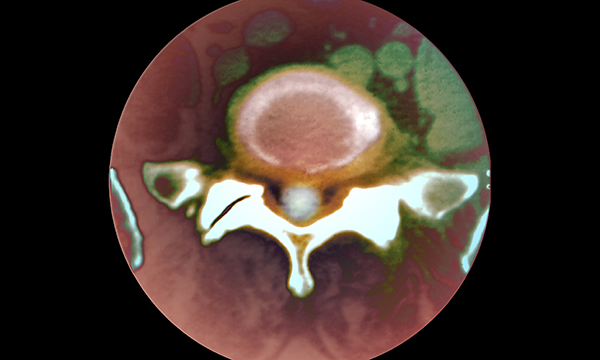

Spinal discs have 24-hour body clocks which can contribute to lower back pain when they malfunction, research shows.